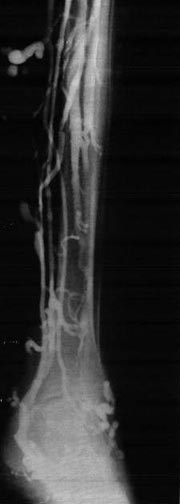

The venous network in the lower extremities commonly affected by CVI is divided into 3 systems. The first is superficial veins, which include the lesser and greater saphenous veins and their tributaries, as depicted in the 1st image below. The second is deep veins, which include the anterior tibial, posterior tibial, peroneal, popliteal, deep femoral, superficial femoral, and iliac veins. The third is perforating or communicating veins, as depicted in the 2nd and 3rd image below.